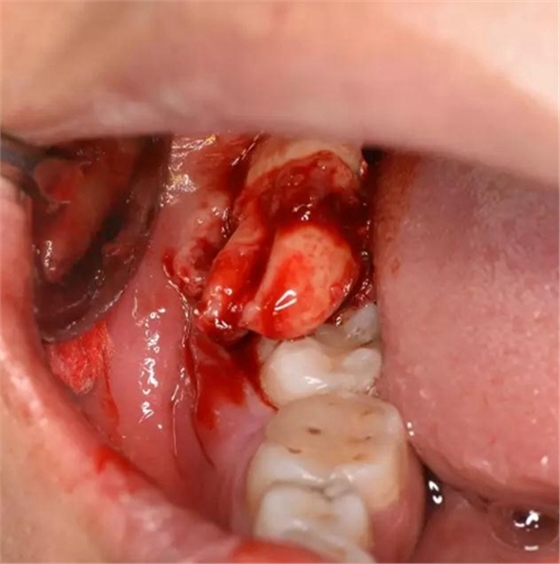

圖9.然后頰側(cè)用挺、挺出48牙齒

圖10.牙齒脫穎而出,48雙根、牙根較大。